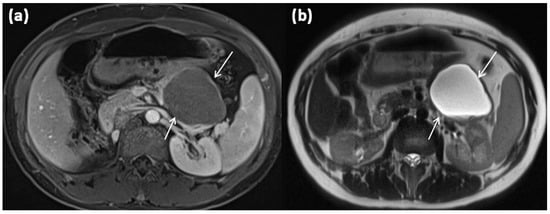

Figure 3.

Axial MRI of a 12-year-old female patient with T1w sequence after gadolinium-based contrast administration (a) and T2w sequence (b). The pancreatic body shows a relatively large, sharply demarcated lesion compared to the surrounding parenchyma, which corresponds to a simple ductal cyst (arrows). No septa or nodular proliferations are detectable, nor are environmental reactions or infiltrative growth present.